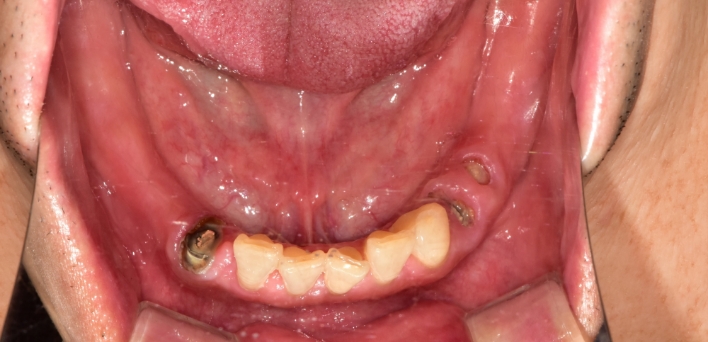

임플란트 : 손 ** 님 (50대)

치아가 있다는게, 아직도 정말 꿈만 같아요.

Before Before

After After

환자 특징

환자 특징01무치악 상태

환자 특징02수년간 무치악으로 지내심

임플란트가 불가능할것이라

생각하고 내원

위, 아래 6개씩 식립

디지털 풀아치 임플란트